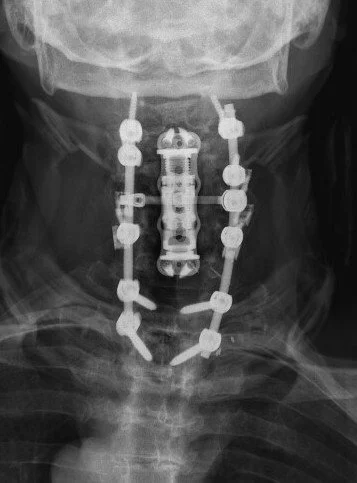

Cervical Spine Revision Surgery

Revision of a cervical spine surgery can be needed for a variety of reasons: failure for bones to fuse (cervical pseudoarthrosis), malposition or failure of implanted hardware, inadequate decompression of the spinal cord or nerve roots, new or persistent neck pain or cervical radiculopathy or myelopathy symptoms, degeneration of neighboring spinal segments, infection, spinal instability, and others.

Management options for a failed cervical surgery might include ACDF, cervical corpectomy, CORUS cervical fusion, or posterior cervical fusion, among others. Each of these options has benefits and drawbacks. The right surgery for you will depend on your symptoms, your previous surgery, the number of spinal levels affected, and factors related to your medical history, age, smoking status, and spinal anatomy.